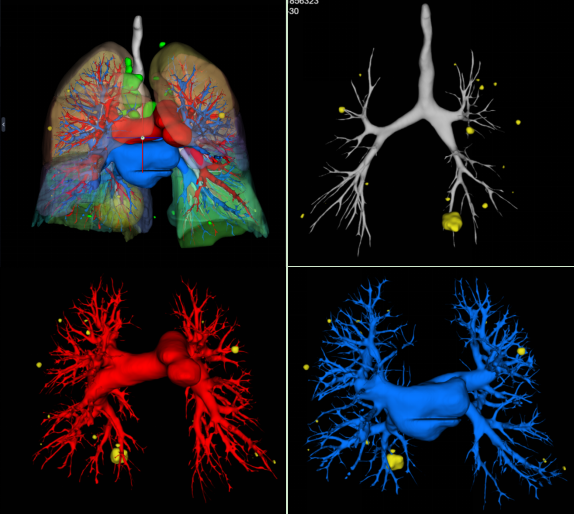

(三)肺結節三維可視化重建CT檢查,可結合原始軸位圖像清晰顯示肺結節與周圍毗鄰關系,尤其是與周圍動靜脈血管的解剖關系,指導臨床手術方式的抉擇。

圖片

肺結節三維可視化重建CT檢查